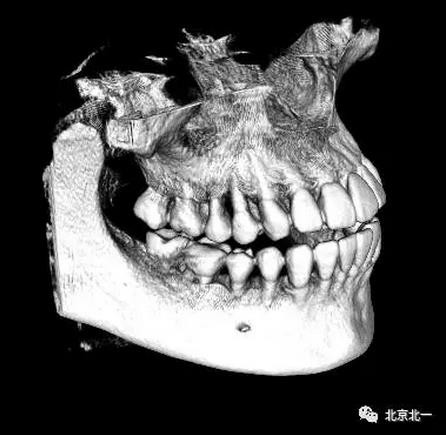

圖四:三維重建